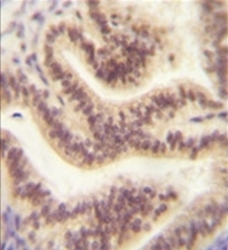

Supportive validation

- Submitted by

- OriGene (provider)

- Main image

- Experimental details

- Formalin fixed, paraffin embedded human uterus tissue stained with C16orf45?Antibody (Center) ??followed by peroxidase conjugation of the secondary antibody and DAB staining. This data demonstrates the use of the CP045 antibody (Center) for immunohistochemistry. Clinical relevance has not been evaluated.

- Validation comment

- IHC